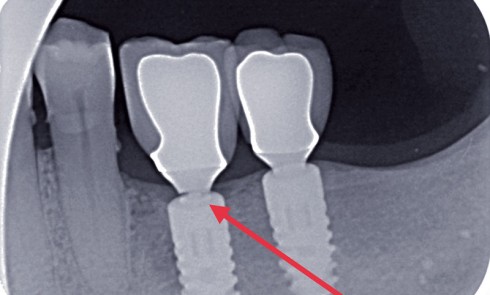

Article réservé à nos abonnés Pronostic des retraitements endodontiques (orthogrades ou rétrogrades) versus implants

Les thérapeutiques endodontiques et implantaires ont un objectif commun : permettre une restauration fonctionnelle et esthétique ayant la pérennité la...